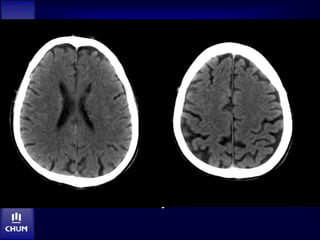

M. N.

Jour 3

• Plus somnolent, mutique

• Parésie jambe gauche

Angio-IRM: jour 3

IRM: jour 3